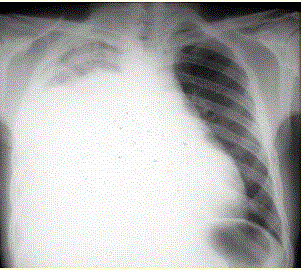

问题  患者男,34岁。进行性胸闷、气促1个月余,伴有干咳、右胸隐痛以及消瘦,无咯血、发热、盗汗、潮热等。 患者的胸腔穿刺结果提示胸腔积液的性质和病因最可能是(提示 患者诊断性胸腔穿刺结果:胸腔积液呈淡红色,细胞数600×106/L,单核细胞65%,蛋白32 g/L,葡萄糖1.8 mmol/L,LDH 550 U/L,ADA 18 U/L,CEA 125 μg/L)

选项 A、类肺炎性胸腔积液 B、结核性胸腔积液 C、恶性胸腔积液 D、渗出性胸腔积液 E、低蛋白血症所致胸腔积液 F、漏出性胸腔积液

答案 CD

解析 CD